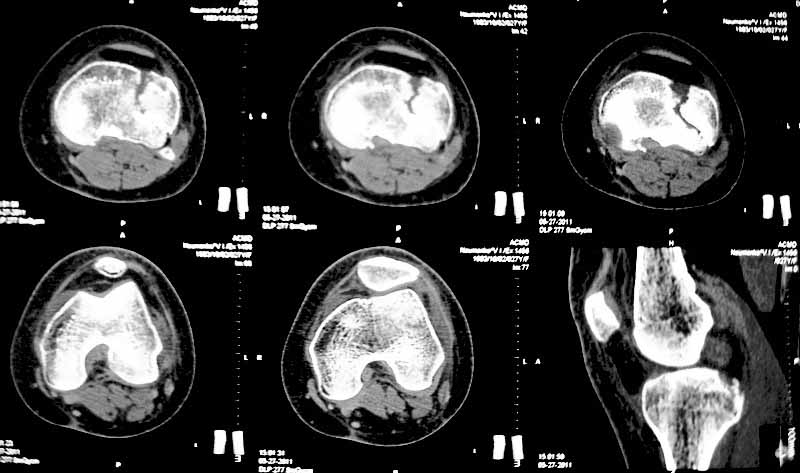

Уважаемые коллеги. Хочу представить вам клинический случай и получить информацию в отношении тактики лечения данной пациентки. Возраст 27 лет, парапланеристка, получила травму в Индии 28 апреля 2011г, упала с мотоцикла, получила боковой удар по левому коленному суставу.

Первая помощь оказана в индийской клинике, установлен диагноз - Ссадины левого локтевого сустава, левого плеча, левой и правой стоп, повреждение связок левого коленного сустава (не указано каких). Со слов пациентки выполнены рентгеновские снимки голени (их не отдали). Наложена циркулярная рассеченная скотч-каст повязка без захвата стопы на левую ногу, рекомендовано консервативное лечение со сроком иммобилизации 6 недель. Пострадавшая оставалась в Индии и вернулась 17 мая.

26 мая обратилась ко мне за консультацией с вопросом – можно ли снять иммобилизацию немного раньше и начать ходить без костылей?. СКТ – снимки прилагаю.

-клинически – вальгизация коленного сустава, умеренная сглаженность контуров сустава, постиммобилизационная контрактура сустава, медиальной и латеральной нестабильности сустава нет.